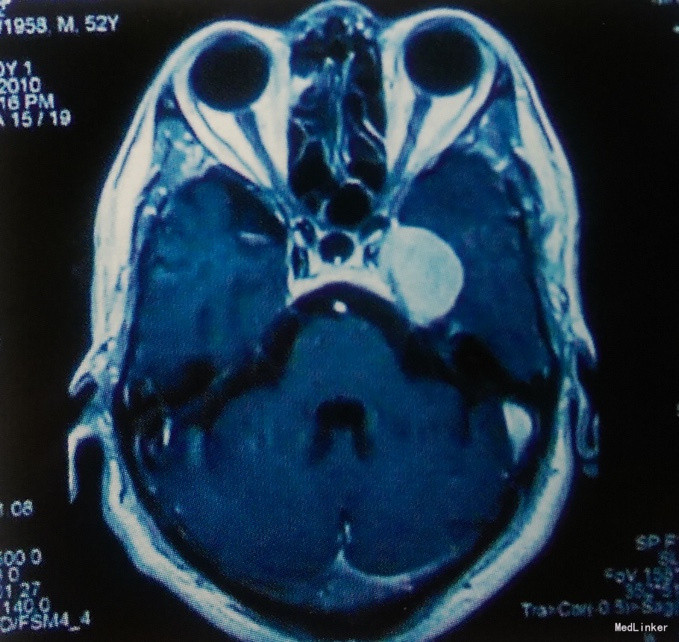

入院查体:体温37℃,脉搏80/min,呼吸20/min,血压110/80mmHg。神志清楚,言语清晰,语言流利,应答切题,查体合作,双瞳等大等圆,直径3.0mm,对光反应灵敏,双眼球各向活动充分。余查体未见异常。GCS评分15分,KPS评分100分。 术前影像学检查 头颅MRI:左侧鞍旁可见一类圆形肿瘤,肿瘤形状规则,强化均一,与左侧中颅窝底及左侧海绵窦硬膜关系密切,可见“鼠尾”征,考虑左侧鞍旁脑膜瘤。